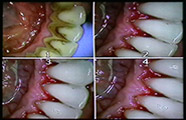

- Detartraj cu ultrasunete si periaj profesional

DETARTRAJ DENTAR EFECTUAT IN CABINET DR. PURGHEL TEODOR

Detartraj